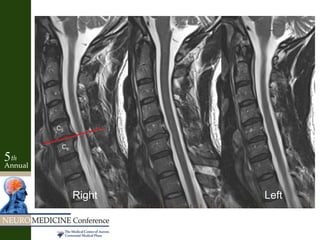

C5-6

C4-5

C7-T1

C6-7C5

C6

C7

T1

C4

• Non-concordant MRI with spinal root palsy

Key Factors • Minimalneck pain, but no radiculopathy into arms – 60 yo so very common symptom • Weakness of hand intrinsics supplied by ulnar nerve only – Maintained median nerve function • Sensory loss in ulnar nerve distribution – Radial half of ring finger spared- not C8 palsy • No reflex abnormalities • No pain or numbness in median nerve distribution to suggest carpal tunnel syndrome – Failed prior carpal tunnel release • Negative Spurling, but +Tinel’s test at elbow • NCS concordant with ulnar neuropathy at elbow • Non-concordant MRI with spinal root palsy